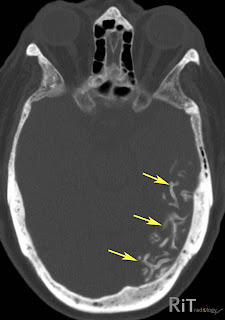

Sturge weber syndrome radiology. Sturge weber syndrome or encephalotrigeminal angiomatosis is a phakomatosis characterized by facial port wine stains and pial angiomas. It is part of a wide. Radiology articles covering imaging techniques findings symptoms diagnosis staging treatment prognosis and follow up. Peer reviewed and up to date.